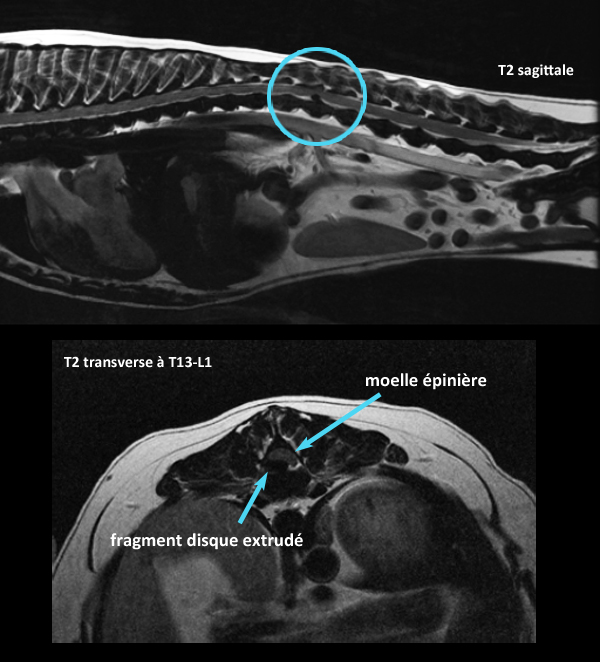

Il y a des chiens pour qui la m…alchance colle aux fesses… En voici un ! Ce petit chien a eu un diagnostic d’extrusion discale aiguë (Hansen type 1) il y a trois semaines par IRM (première image ci-bas), avant d’aller en chirurgie. Il a très bien récupéré, jusqu’à développer de nouveau des troubles neurologiques, cette fois localisés T3-L3. Bang !!!! Une nouvelle extrusion discale à T13-L1 (image du bas) ! C’est ce qui s’appelle des extrusions « back-à-back », ou « neck-à-back »… ;-(